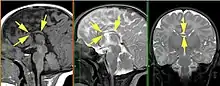

Основные диагностические критерии, позволяющие заподозрить наличие АМТ:

- радиальный паттерн борозд медиальной поверхности мозга — борозды медиальной поверхности гемисфер мозга отходят от крыши III желудочка, поясная извилина не сформирована;

- параллельность тел боковых желудочков головного мозга

- расстояние между телами боковых желудочков увеличено

- аномальное расширение задних рогов боковых желудочков

- отсутствие прозрачной перегородки

- высокое расположение III желудочка.